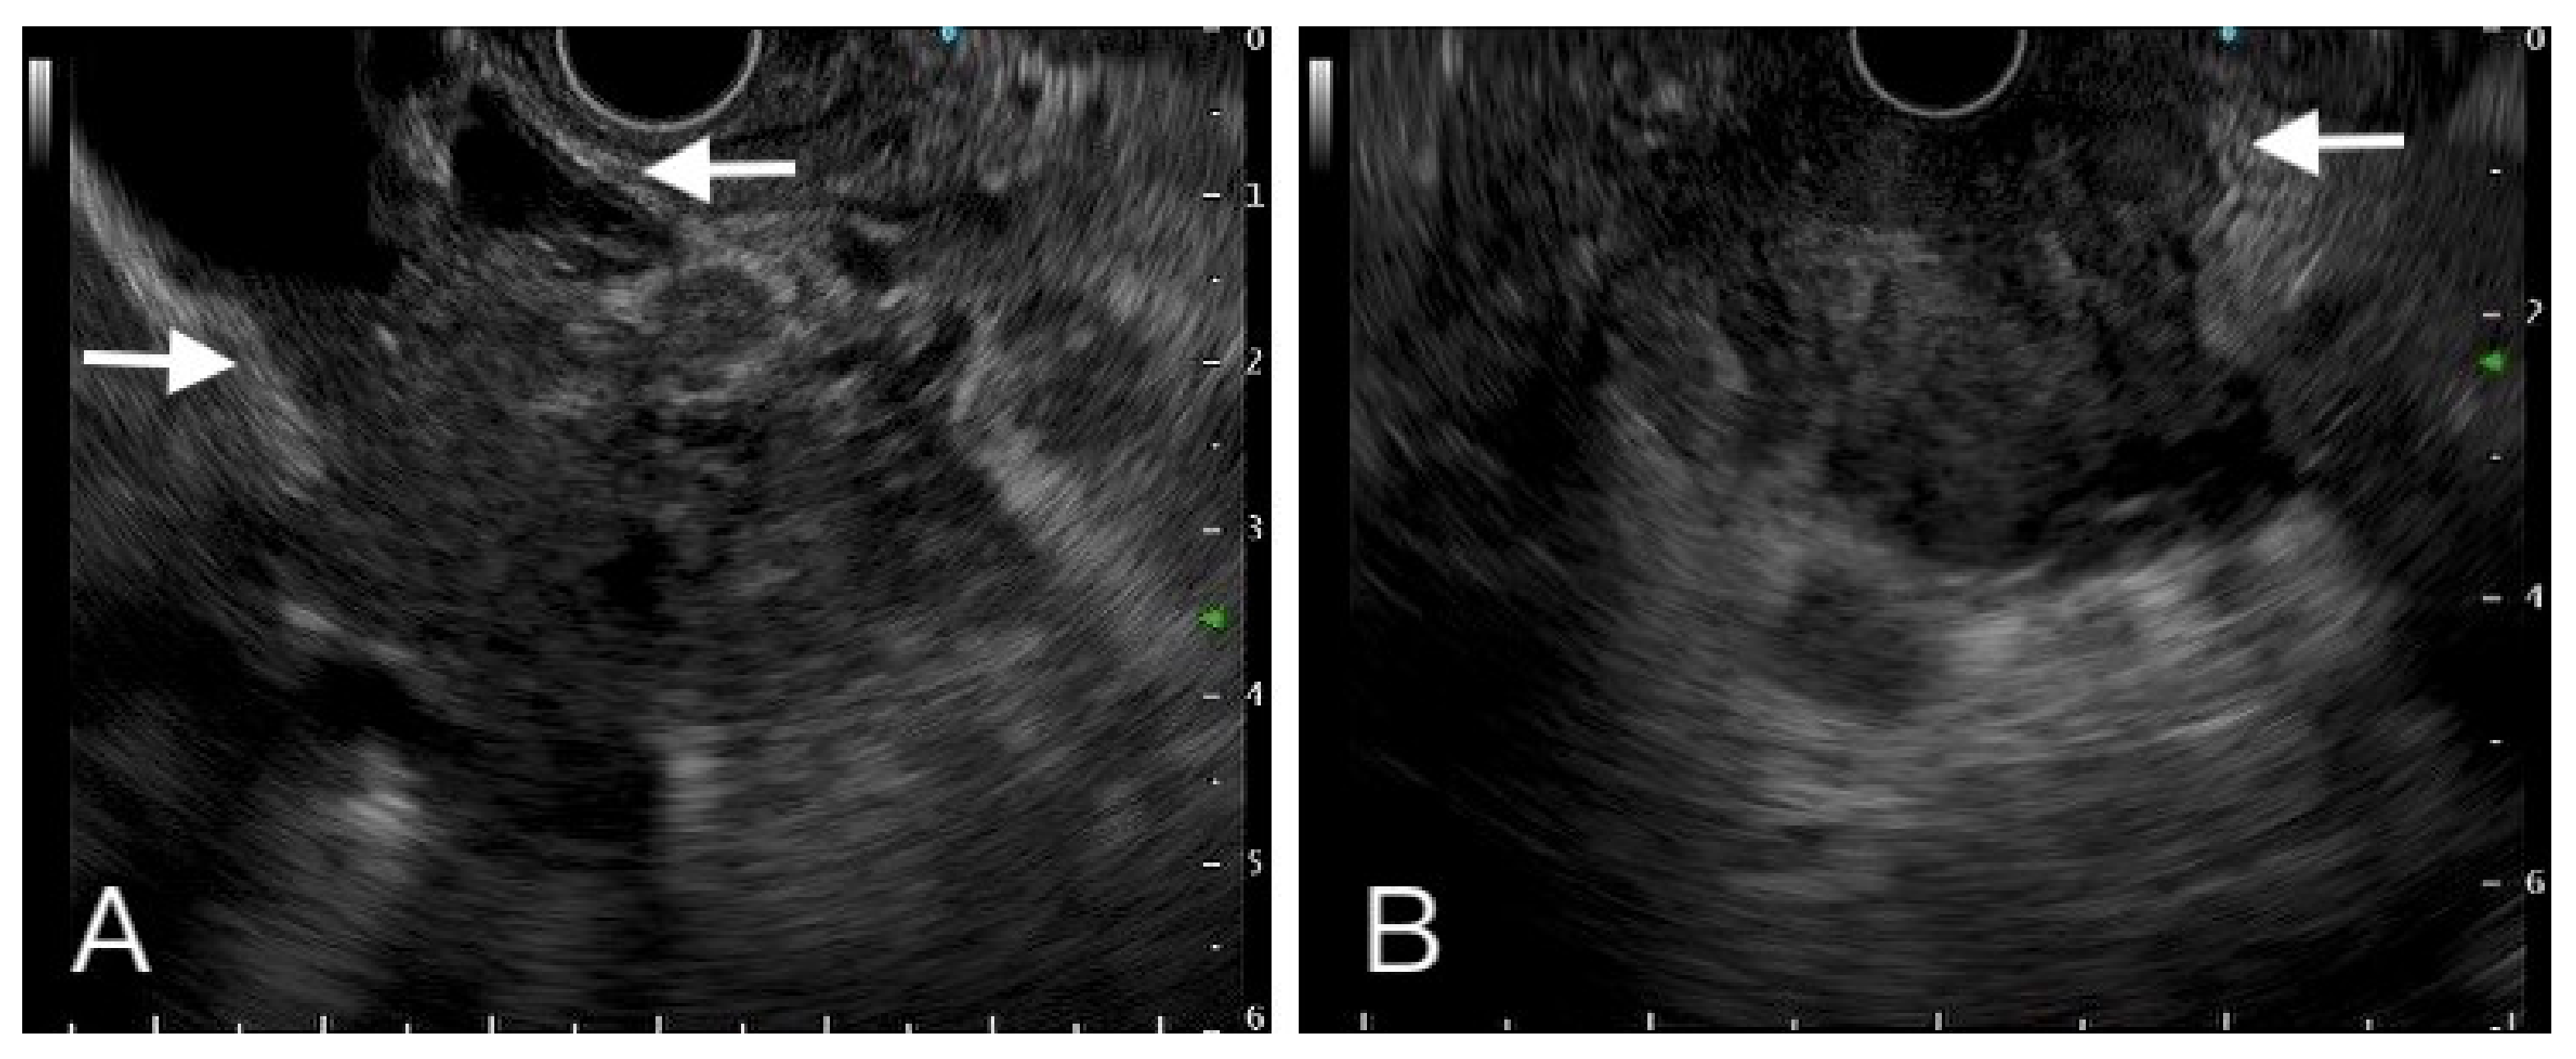

Figure 3.

A hypoechoic heterogeneous mass had ill-defined margin with vessel (left side arrow), common bile duct (right side arrow) (A). Another one hypoechoic mass invaded to duodenum (B). Tissue proof by FNB showed these two tumors were adenocarcinoma.